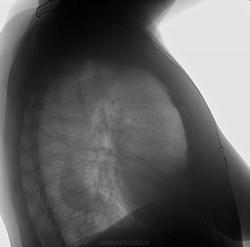

Аневризма дуги аорты?

Дебют. Может ли тень в проекции дуги аорты объяснена иначе, чем аневризма? Нужны ли в таком случае дополнительные методы исследования? Спасибо!